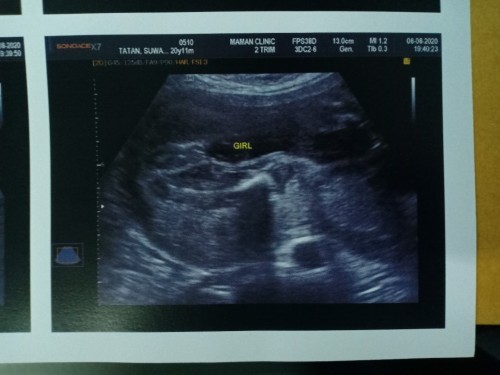

6เดือนนิดๆค่ะ

Post reply image